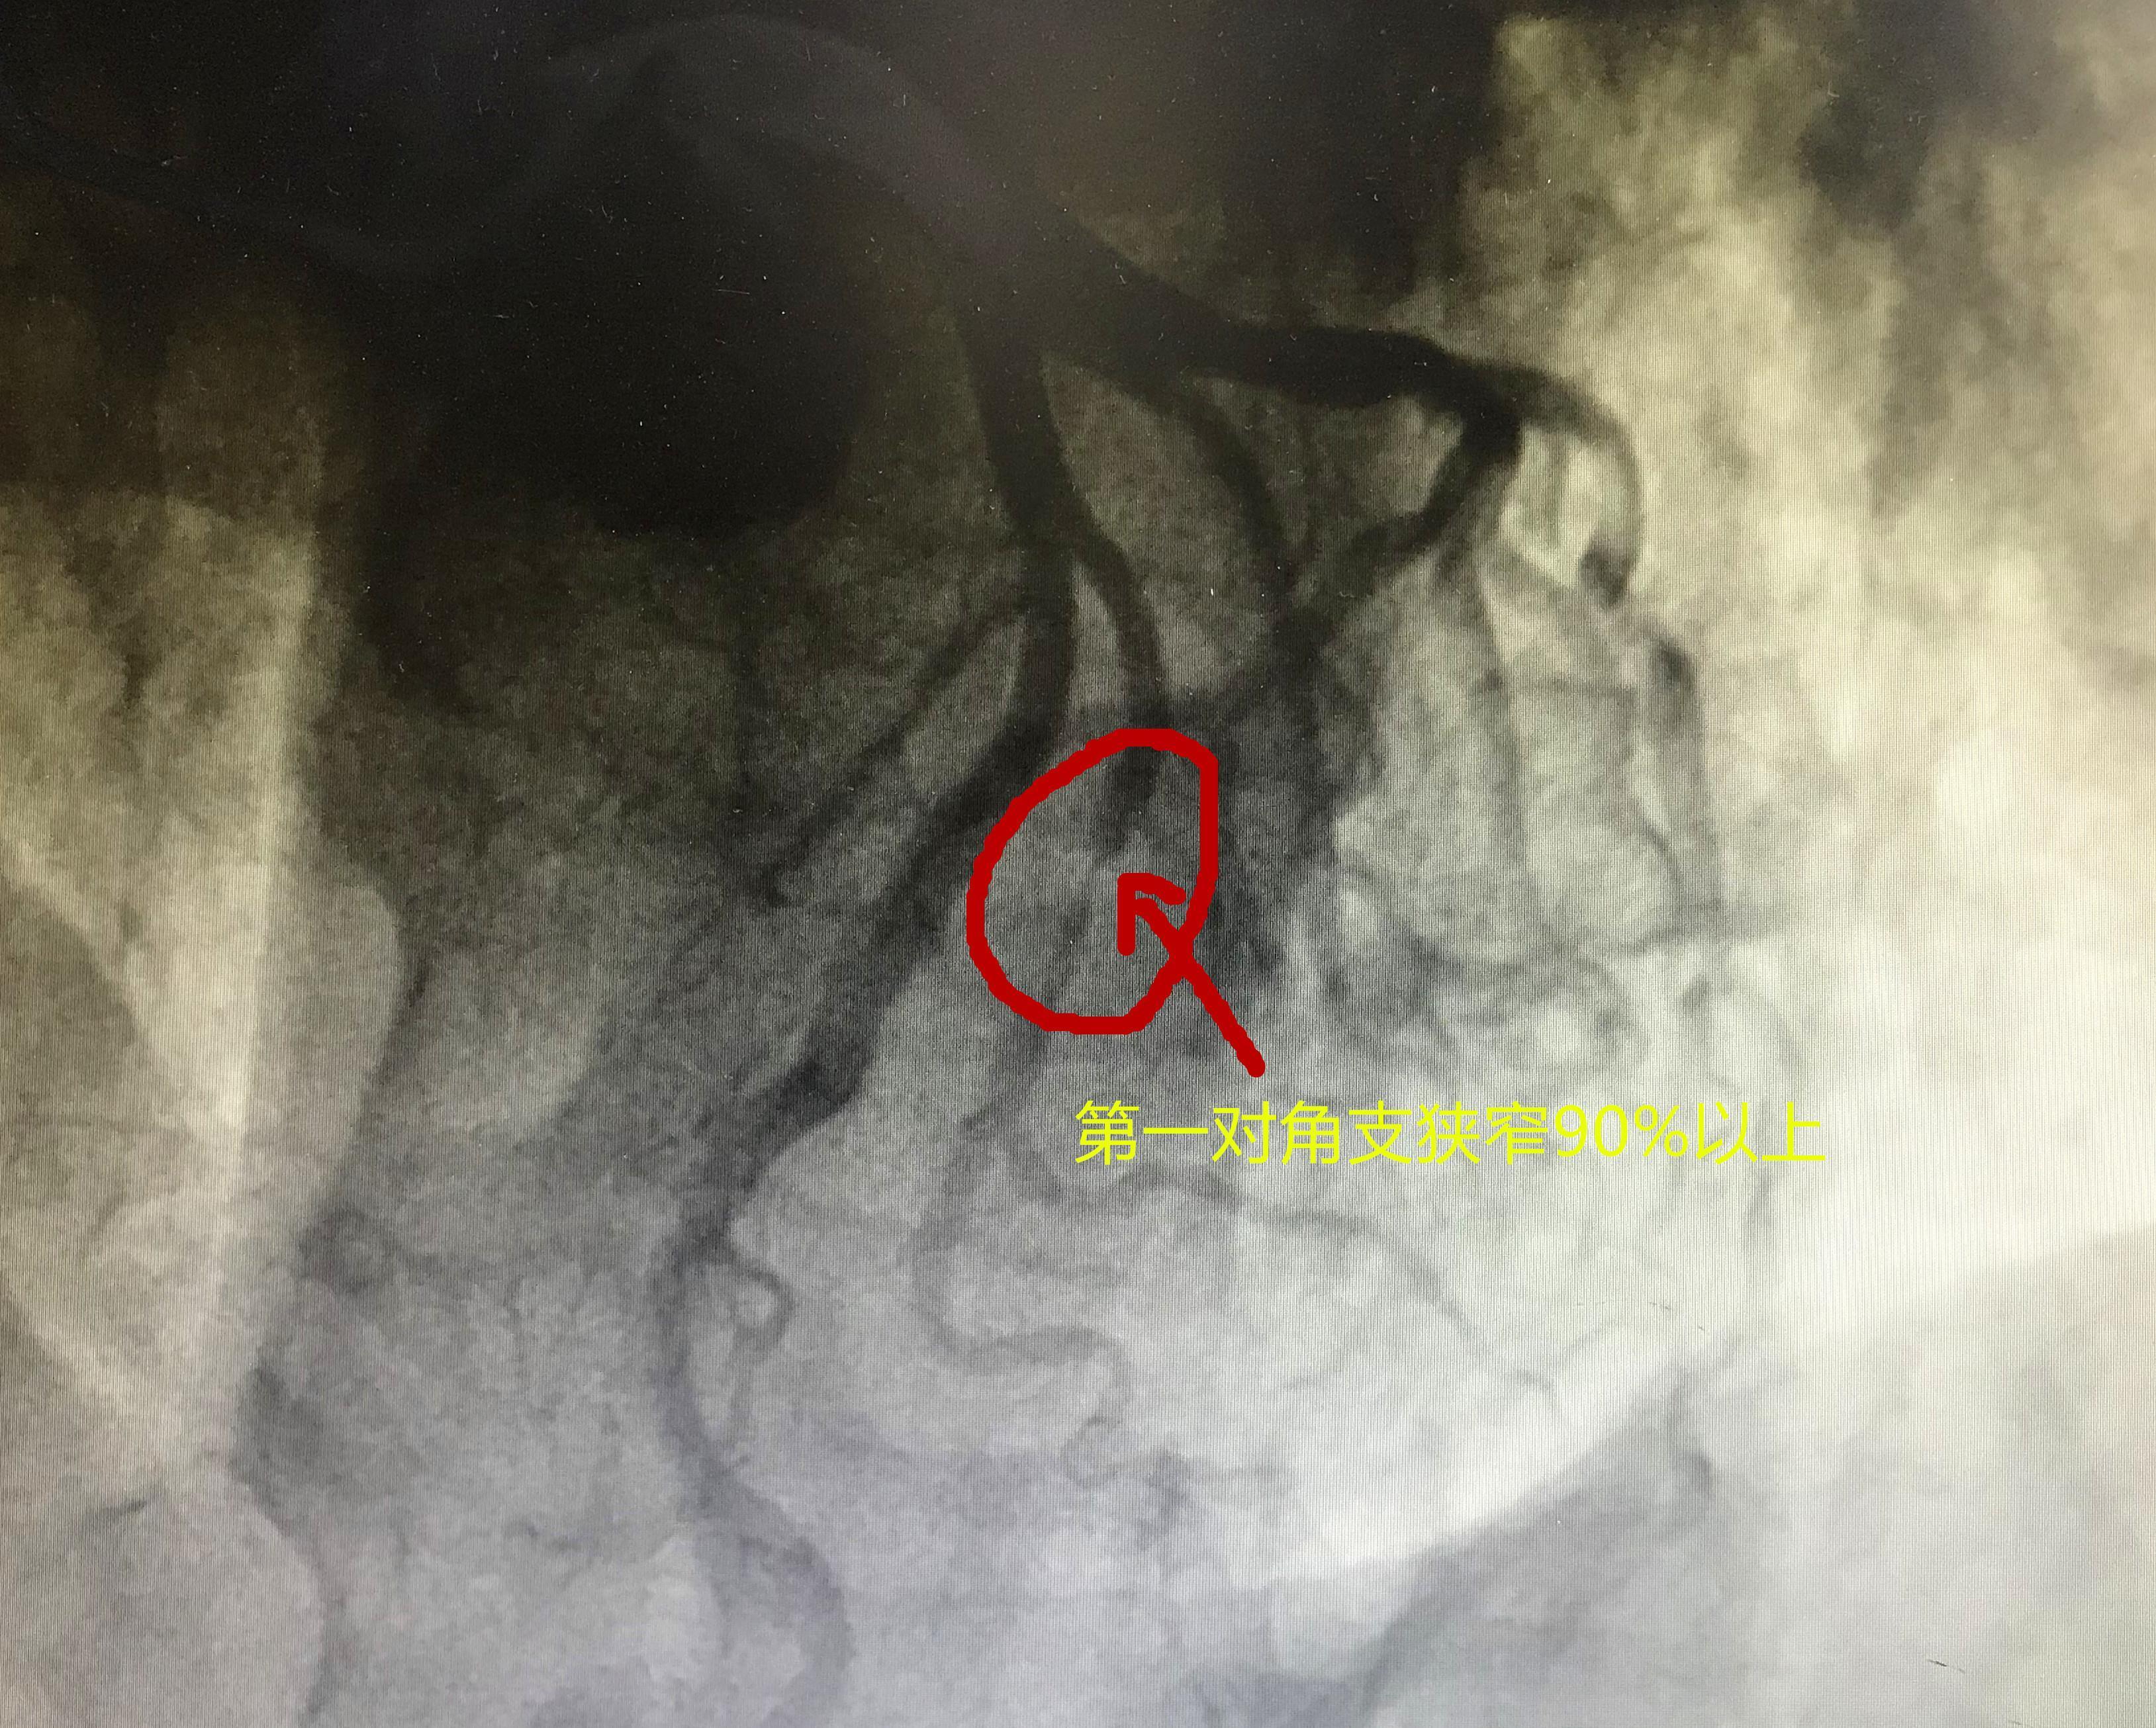

血管造影结果显示,老人有一支比较大的血管几乎堵死了,超过90%以上堵塞。我们分析,老人反复发作心绞痛和这个血管有直接关系,当血管严重供血不足的时候,除了会有胸闷胸痛,由于心肌的严重缺血缺氧,还会造成心功能下降,出现心源性哮喘发作。

文章插图

冠脉造影显示血管高度狭窄